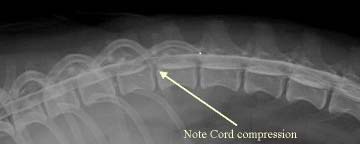

A

myelogram

(right) is an x-ray of the spine, taken after the dog’s spine has been

tapped and cerebrospinal fluid (CSF) has been injected with a dye, to enhance

the view of the spinal cord. The procedure requires a spinal tap, and therefore

the dog must be under general anesthesia. The myelogram should enable the

examiner to locate the affected disc and the precise location of where the disc

is impacting the nerve roots, spinal cord, or surrounding tissues.

However, due to the predominance of syringomyelia in the cavalier King Charles

spaniel, myelography is deemed to be risky in this breed. See this

2005 report.